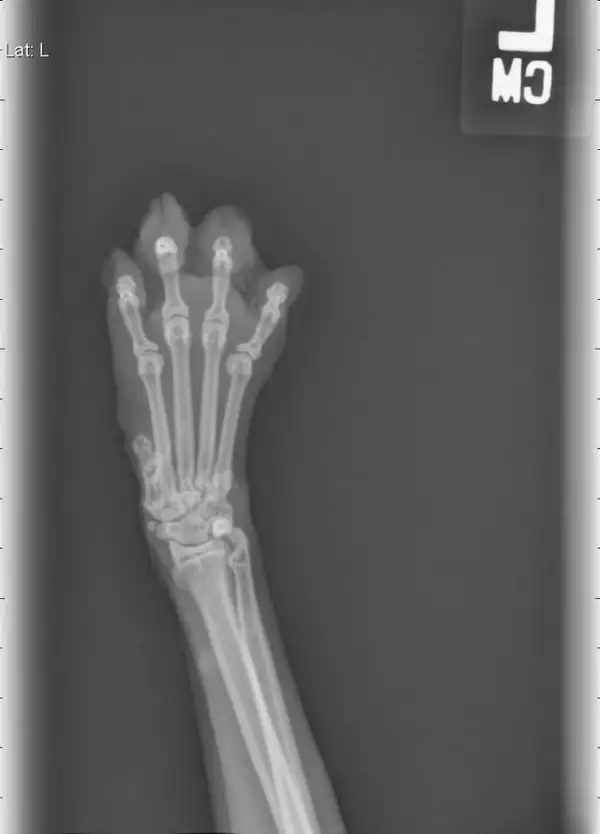

Рука пианиста, который играет 30 лет